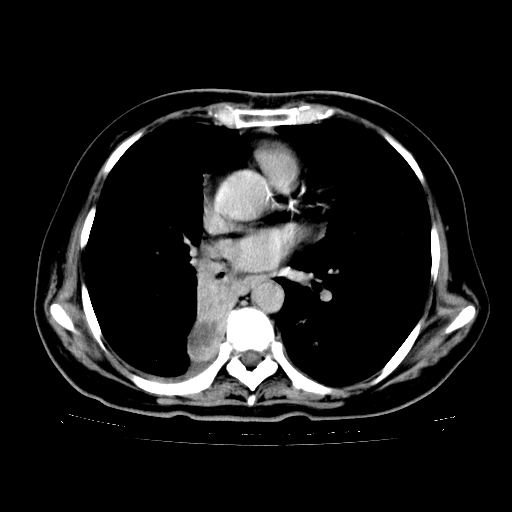

标题: CT23067:女,70岁,咳嗽、咳痰一个月,低热一周。 [打印本页]

女,70岁,咳嗽、咳痰一个月,低热一周。

2.胸主动脉夹层。

支持,首先一元论解释。胸主动脉部分层面环形低密度,中心强化。环形影不强化。不象真假腔的改变。我考虑动脉炎,不太支持夹层动脉瘤-和大家的观点不一致,希望楼主让患者再做个心血管的彩超吧。

继发型肺结核,右下肺支气管内膜结核.右侧少量胸腔积液.主动脉夹层.